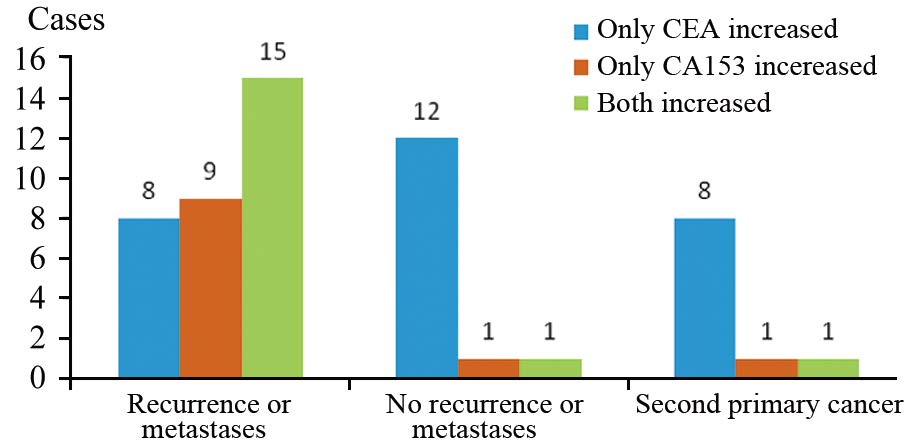

ResultsOf all 56 cases, there were twocases of local recurrence, 30 cases of metastasis, 14 cases without recurrence and 10 cases of second primarytumor. 18F-FDG PET/CT imaging was positive in 41 cases (one false positive case), negative in 15 cases (twofalse negative cases). The diagnostic efficiency of 18F-FDG PET/CT were: sensitivity 95.24%, specificity92.86%, accuracy 94.64%, false negative rate 4.76%, false positive rate 7.14%, positive predictive value(PPV) 97.56%, and negative predictive value (NPV) 86.67%. The PPV of increased CEA alone, increasedCA153 alone and their combination were 57.14%, 90.91% and 94.12%, respectively (χ2=10.430, P=0.005).

Conclusion18F-FDG PET/CT can be used to identify or rule out the recurrence and metastasis in breastcancer patients with increased serum CA153 and(or) CEA after treatment, with high diagnostic efficiency andgood clinical application value. And it can also suggest the second primary tumor.

表 2 18F-FDG PET/CT显像阳性对PPV的作用

Table 2 Effect of positive 18F-FDG PET/CT imaging on PPV